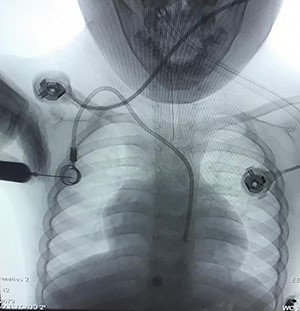

Case 3—a 5-year-old male child was diagnosed as having Hodgkin’s lymphoma during the evaluation of cervical lymphadenopathy and weight loss. He was planned for chemotherapy, and a central vein chemo port was implanted in a pediatric hospital. They took a chest X-ray (Fig. 4) after the procedure and understood the catheter is in the carotid artery instead of the jugular vein so they consulted with us and sent the child in <4 h to our vascular surgery operating room. We prepped and draped the neck of the child and removed the catheter from the carotid artery and packed it for 20 min. The child discharged the next day without any complication, and 10 days later in the clinic, he was fine.

Chemotherapy port catheter in the carotid artery of a 5-year old child.